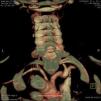

Around four months later, there was recurrence of exertional angina. At this time a difference in blood pressure between the arms was noted (20 mmHg less in the left arm), with a very weak pulse on the left and evident skin pallor immediately after exertion or when raising the left arm. Laboratory testing showed slight thrombocytosis and a rise in erythrocyte sedimentation rate to 100 mm/h. Echocardiography revealed new-onset hypokinesia of the left ventricular inferior wall, and coronary angiography was repeated, which showed preocclusive lesions of the right coronary artery and ostial saphenous graft. She underwent percutaneous coronary intervention with placement of two drug-eluting stents; during the procedure occlusion of the left subclavian artery was observed with retrograde filling from the ipsilateral vertebral artery (Figure 1), which raised the suspicion of Takayasu arteritis. Cranial computed tomography (CT) angiography confirmed proximal occlusion of the left subclavian artery upstream of the origin of the left vertebral artery (Figure 2), an atheromatous plaque in the distal segment of the right common carotid causing preocclusive stenosis of the external carotid, and tortuosity and kinking of the cervical course of the internal right carotid artery. Carotid Doppler ultrasound showed coiling of the right internal carotid and 70% stenosis, preocclusive stenosis of the right external carotid and reversal of flow in the left vertebral artery caused by left subclavian steal. Abdominal Doppler ultrasound detected no abnormalities in the renal arteries and the patient did not present nitrogen retention. In view of these findings and fulfillment of the diagnostic criteria, a diagnosis of Takayasu arteritis was made and therapy was begun with oral prednisolone 1 mg/kg/day.